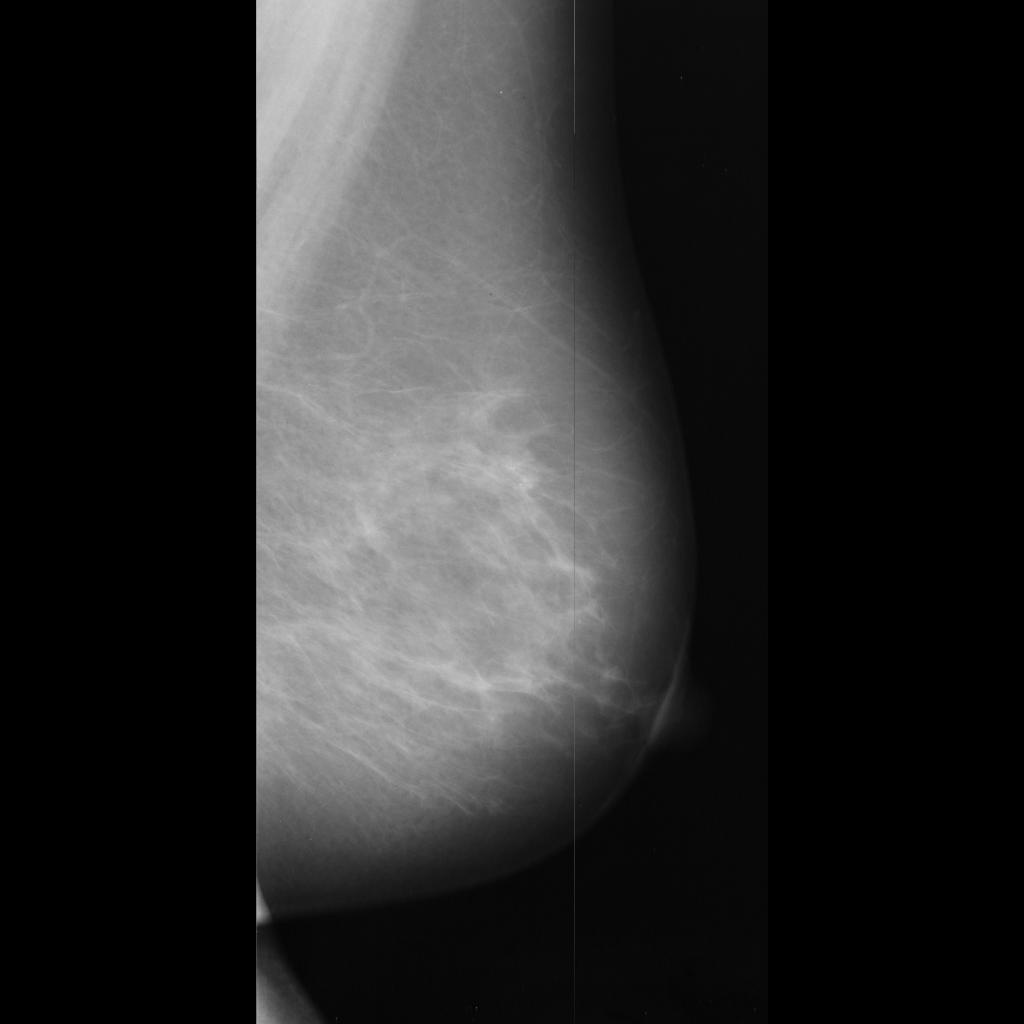

benign